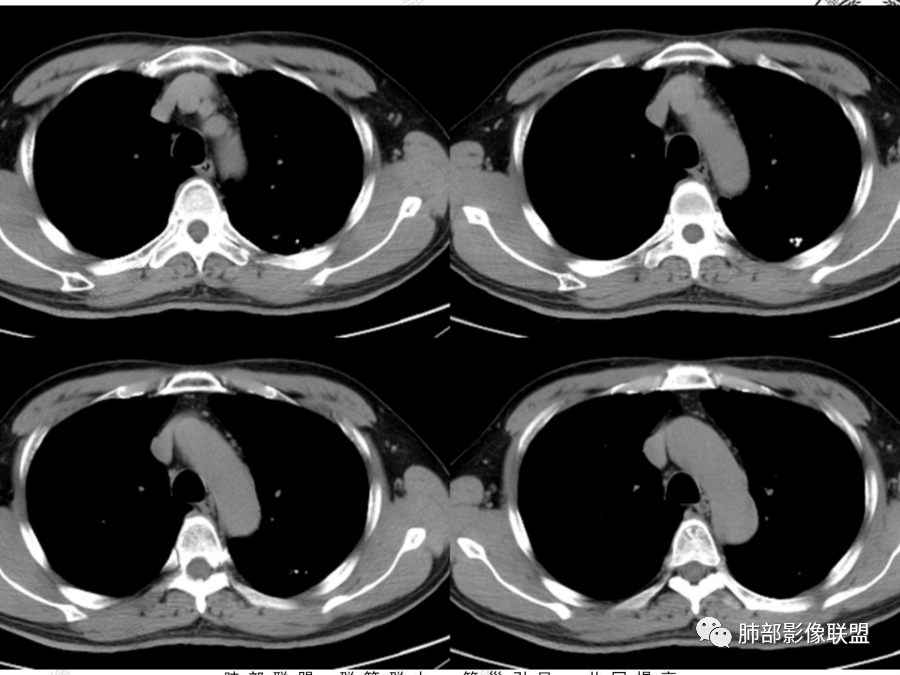

左肺下叶空腔,分隔状,壁厚薄不均,支气管截断,部分周围可见磨玻璃影,胸膜牵拉,左肺上叶多发结节,部分可见钙化,考虑1左肺下叶囊腔型腺癌。2左肺上叶结核。

中年男性,多发空腔,腔内可见分隔、壁结节。考虑:囊腔型腺癌。肺结核为陈旧性。

男51,体检发现肺部阴影,左肺下叶见多发薄壁囊腔影,可见结节,囊腔内见分隔,轻度胸膜牵拉,病灶周围少许磨玻璃影,常规考虑囊腔型腺癌,肿瘤标志物不高,除外结核。

中年男性,体检发现,吸烟史,但肺气肿背景不明显。左肺下叶囊腔病变,有一定张力,分隔明显,似有多个囊腔融合感,部分边缘见少许磨玻璃影,有支气管截断,首选囊腔型肺癌,某些先天病变(囊腺瘤样畸形等)也要考虑。

左肺上叶钙化结节,边界清楚,周围散在多发小结节,伴有磨玻璃影,考虑结核可能,左肺下叶多个囊堆积而成,大小不一,其内可见分隔,囊壁厚薄不均,病变近端与支气管相贴,支气管似扩张,考虑CCAM,鉴别囊腔性腺瘤,囊腔性腺癌

肺结核背景,左下肺簿壁囊腔,内有分格,有支气管截断,囊壁局限性增厚,嗜烟史,考虑左下囊腔型肺癌(鳞癌)。

左肺上叶陈旧肺结核,以增殖钙化灶为主,左肺上叶多发囊泡样结节,有分隔,稍分叶,周围少许磨玻璃,支气管部分截断,部分贴边穿过,老年男性,考虑囊腔型腺癌。

左肺上叶多发小结节影,部分钙化,考虑结核。左肺下叶多个囊状影,腔内见血管影,间隔稍粗大,考虑囊腔型肺癌,

老年,51岁男性病人,左上肺斑点,小结节状阴影,可见钙化,陈旧性肺结核改变,患者有长期的吸烟病史。左肺下叶背段多个囊腔肿块影,整体呈团块状类圆型,无明显壁结节,整体病灶张力较大,具备一定的膨胀感 ,支气管拉直并有突然截断改变,考虑囊腔型鳞癌。鉴别诊断:结核性病变,局限性囊性支气管扩张

男性,体检发现左肺阴影。影像表现:左上肺多发结节伴纤维条索影,部分钙化,左下肺囊腔样改变,内有分隔,部分分隔边缘见实性成分及GGO样改变,支气管从旁边经过,或受压,无明确进入依据。初步诊断:1、左上肺结核。2、左下肺囊腔型腺癌,诊断依据:分隔样囊腔,部分分隔有实变,边缘有GGO改变,鉴别诊断:1、囊腺瘤样畸形,分隔样囊腔要考虑,但部分分隔实变,部分伴GGO样改变成疑,最大的疑问是年龄51岁,体检发现,抽烟、饮酒30年,却无发病,可能性太小。2、囊腔性转移,单发分隔样囊腔转移少见,且需要病史支持。3、囊性淋巴瘤,一般以单发囊腔多见,分隔样囊腔型淋巴瘤罕见。4、感染,无相关临床症状及辅检支持,基本排除。